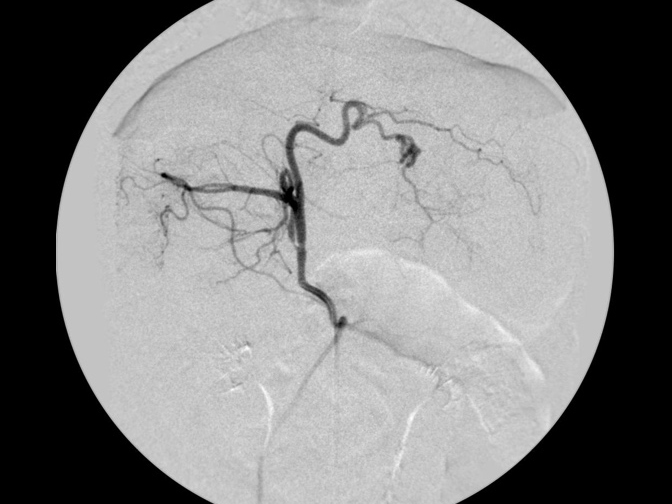

カテーテルでの造影検査

造影での腫瘍の評価